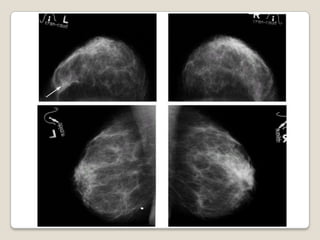

   Nódulo / Masa

   Microcalcificaciones

   Deformidad del parénquima

   Asimetría

   Lesión Espiculada

Signos Mamográficos

 Zona de mayor densidad del tejido

mamario

 Bordes bien definidos : P. benigno

 Bordes mal definidos : p. maligno

◦ Lesión ESPICULADA, en principio Maligna

◦ Siempre requiere estudios complementarios

◦ Ecografía, PAAF / BIOPSIA

Nódulo / Masa

 Menores de 35 años, el diag. Más

probable es FIBROADENOMA

 Entre 35 y 45 años, los Quistes son más

frecuentes

 Mayores de 55 años, más probabilidad de

CARCINOMA.

Nódulo: probable diagnóstico

según la edad